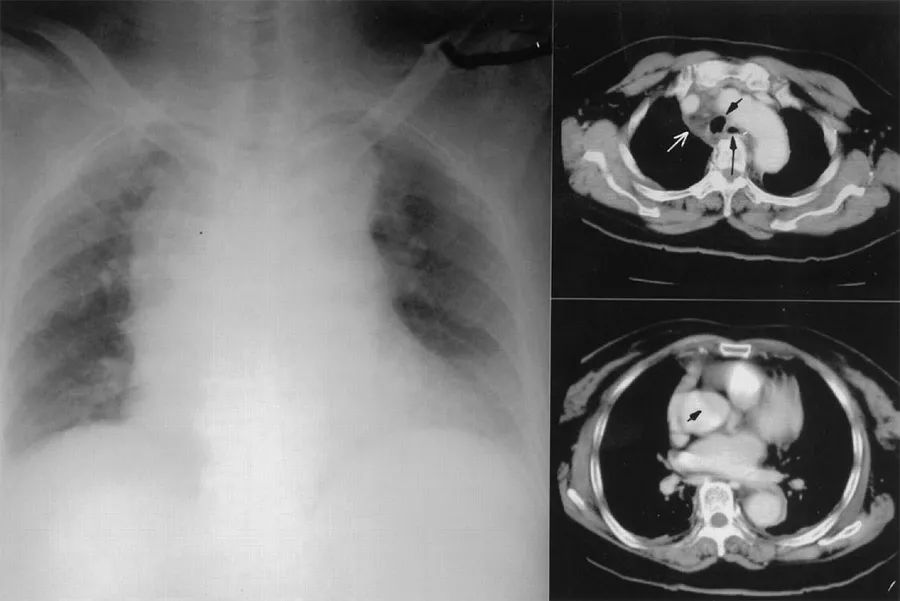

患者女性,41岁,因胸骨后疼痛2小时被送入急诊室。患者自述胸痛向肩胛间区放射,入院前几天一直有流涕、咽痛、咳嗽、呕吐。既往健康,无冠心病危险因素。

查体及常规实验室检查均正常,胸片显示右侧胸腔积液,无纵膈气肿和皮下气肿(图5)。心电图提示胸前导联ST段压低、T波倒置,超声心动图未见明显异常。入院6小时后复查心肌酶仍为正常,心电图无动态改变。实验室检查发现患者入院6小时的血红蛋白由130 g/L降至110 g/L。

图5 入院时胸片

患者恶心、呕吐加重,仍有持续胸痛。于是,进行了CT检查(图6),发现纵膈内少量积气、食管下段周围积液。患者接受了手术治疗,术后恢复良好。

图6 入院6小时后CT检查